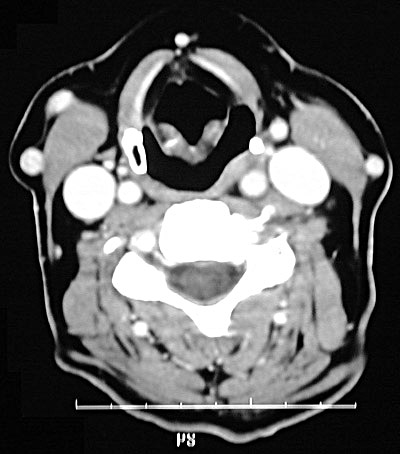

| In this CT scan of the neck region, there is a pulsion diverticulum of the esophagus. Such a diverticulum represents enlargement and outpouching of esophagus through constrictor muscles. Such a lesion is also known as a Zenker's diverticulum. This lesion can produce a mass effect, interfere with swallowing, and collect food that decays and produces marked halitosis. |